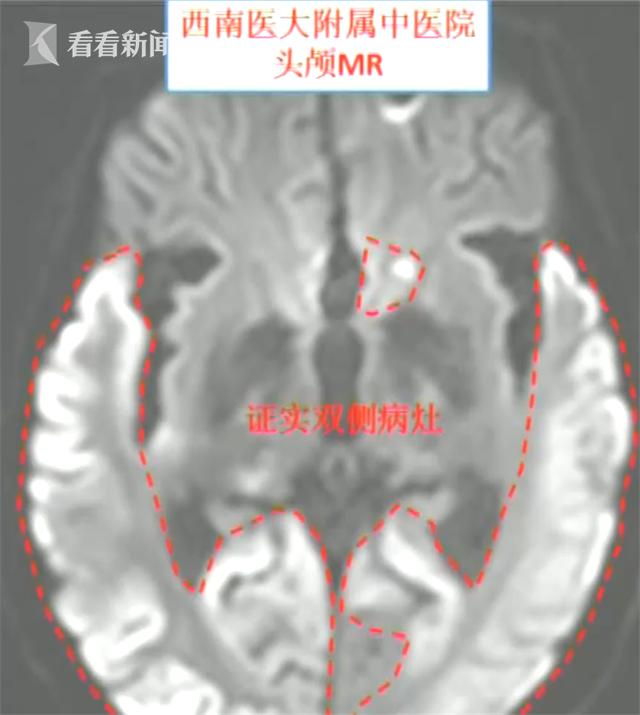

今年2月,在泸州,66岁的缪大爷因为右侧手脚无力和胡言乱语等症状被家人送到当地医院救治,医生诊断是"左侧脑梗死",也就是缺血性中风。经过治疗,病情没有好转,20天后,缪大爷的头部CT显示,在"左侧脑梗死"基础上他又新发了"右侧脑梗死"。有加重迹象。

刘天助告诉记者,当时他结合缪大爷的家族史,确诊大爷的病症是MELAS综合征,也就是线粒体脑肌病伴乳酸血症和卒中样发作,是一种罕见疾病,并不是中风。